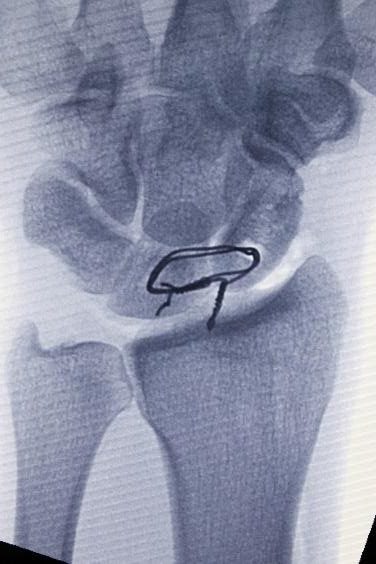

Aşağıda gösterildiği gibi, instabiliteyi sabitlemek için volar ve dorsal ligamanın skafolunatını tendon grefti ile yeniden yapılandırmak genellikle tercih edilen prosedürdür.